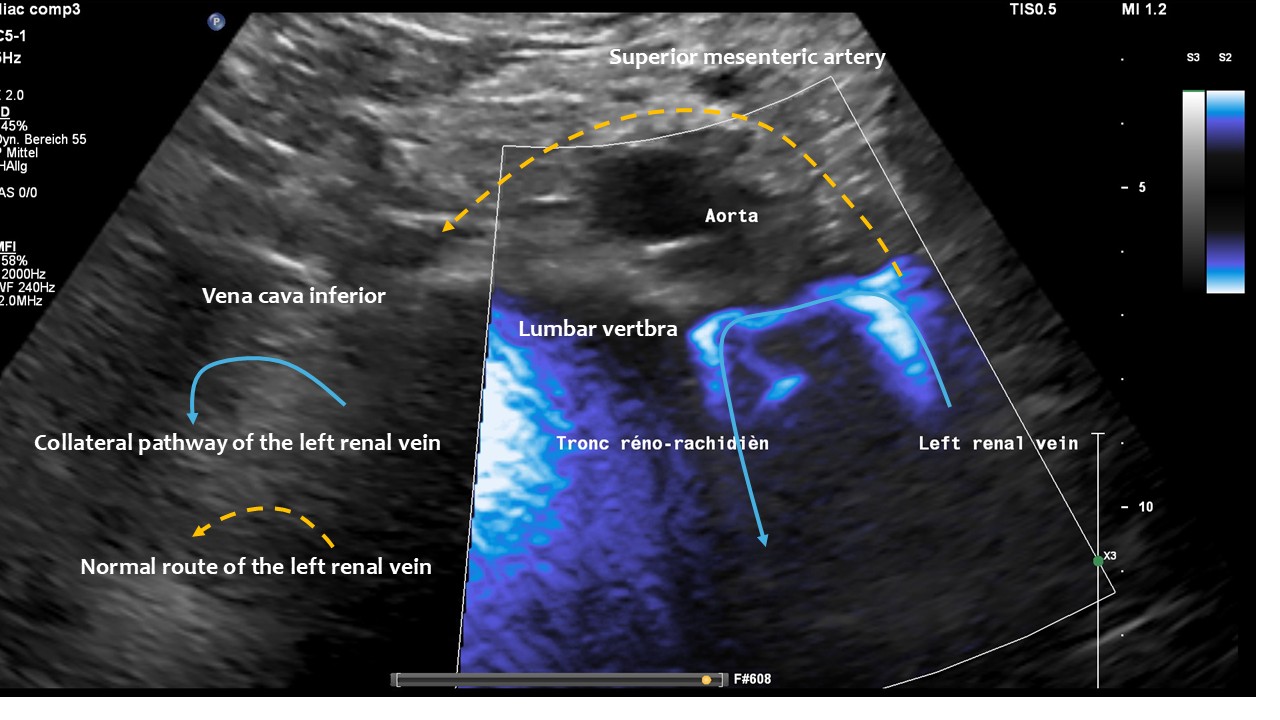

Rather than being located between the superior aorta 100, the left renal vein curves around the left lateral circumference of the spine, draining blood to the spine via a strong vessel known as tronc réno-rachidièn . Additionally, a very narrow retroaortic second left renal vein is present.

These images, taken from the front of the patient, show the tronc réno-rachidièn. This vessel runs in a U-turn along the left side of the lumbar spine towards the back, entering the intervertebral foramen and thus putting pressure on the spinal canal. They demonstrate that the preaortic portion of left renal vein (yellow dashed arrow) does not carry any blood, meaning that all of the left renal venous blood must be diverted via the tronc réno-rachidièn. The other natural collateral pathway, the left ovarian vein, is less significant here. In this patient ( as in many arteries with left renal vein compression) , the collateralisation via the left ovarian vein towards the pelvic venous circulation is obstructed by compression of the left common iliac vein. This combination is very common and requires simultaneous treatment of both the left renal vein and the left common iliac vein in one operation, by shielding both with a PTFE shield.